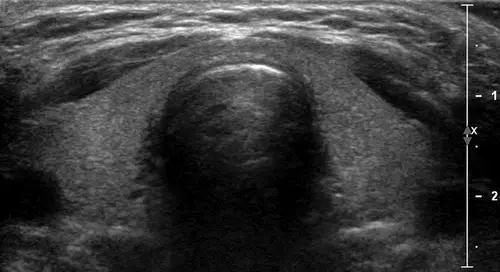

سونوگرافی تیروئید از امواج صوتی برای تولید تصاویری از غده تیروئید در گردن استفاده می کند. از پرتوهای یونیزان استفاده نمیکند و معمولاً برای ارزیابی تودهها یا گرههایی که در طول معاینه فیزیکی معمول یا سایر معاینههای تصویربرداری یافت میشوند، استفاده میشود

برای انجام سونوگرافی تیروئید بیمار روی تخت دراز می کشد سپس پزشک ژل را روی ناحیه جلوی گردن میریزد ژل بر پایه آب بوده و هیچ گونه حساسیتی ایجاد نمی کند و پروب سونوگرافی روی ناحیه مذکور قرار می گیرد و با استفاده از امواج صوتی با فرکانس بالا تصاویر دقیق از تیروئید و پاراتیروئید و نواحی گردن ایجاد می کند.

ندول های تیروئید بسیار شایع هستند. بیش از نیمی از افراد حداقل یک ندول در تیروئید خود دارند که اکثریت این ندول ها خوش خیم و غیر سرطانی هستند و حتی بیشتر آنها بر عملکرد تیروئید تاثیر نمی گذارند. با این حال ممکن است برخی از این ندول ها حاوی سلول های سرطانی باشند که برای بررسی های بیشتر نیاز به سونوگرافی و در برخی موارد نیاز به نمونه برداری و بررسی آزمایشگاهی دارد.